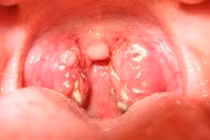

(khoahocdoisong.vn) - Viêm amidan hốc mủ là một dạng mạn tính của bệnh viêm amidan. Đây là chứng bệnh khó chữa và gây rất nhiều phiền toái cho người mắc. Dưới đây là 3 bài thuốc đặc trị viêm amidan hốc mủ rất tốt cho bạn.